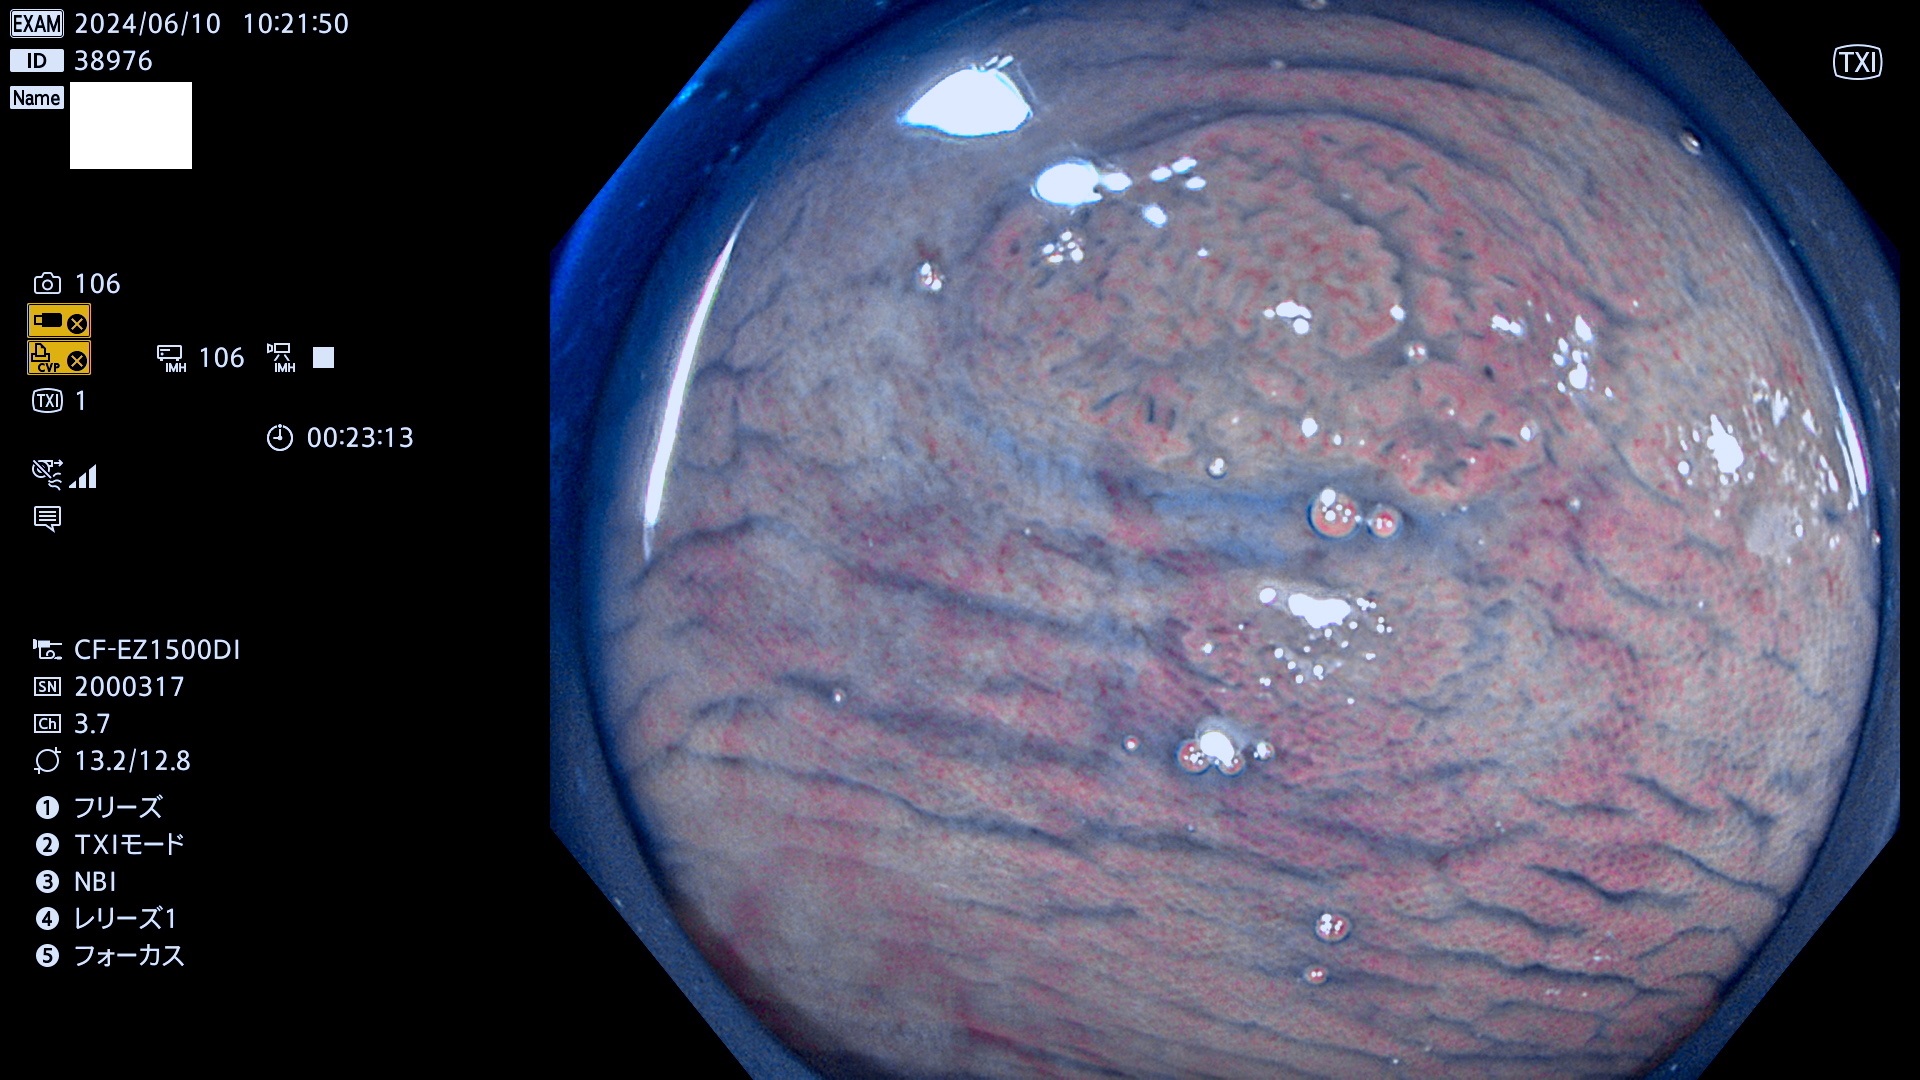

今週のUb、Uc型腺腫

表面型腺腫(Flat Adenoma)の中で、完全に平坦な物をUb、陥凹している物をUcと呼びます。平坦隆起型(Ua)よりも、発見が難しく危険な病変です。

毎週の検査(木・金・土・日)に発見されたUb、Uc型・腺腫を、その週の日曜の夜にUPし1週間、提示します。

抽出の対象期間 2024年6月6日〜6月10の5日間(50件の検査)7件 (7/50=14%)